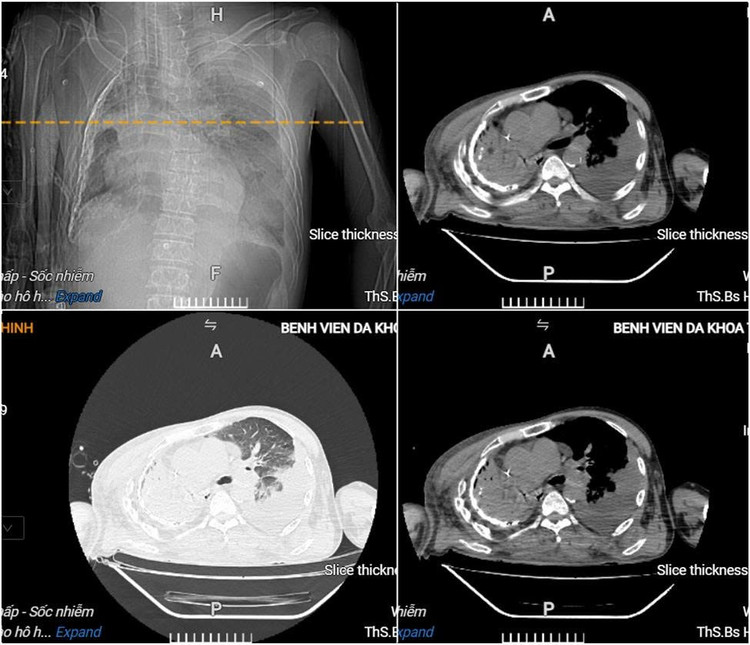

Kết quả xét nghiệm ghi nhận toan chuyển hóa, suy đa tạng, nhiễm trùng – nhiễm độc nặng, rối loạn đông máu. Hình ảnh chụp CT ngực cho thấy có áp-xe phổi trái lớn, tràn dịch màng phổi phải.

Hình ảnh cắt lớp vi tính lồng ngực của người bệnh cho thấy có áp-xe phổi trái lớn, tràn dịch màng phổi phải - Ảnh BVCC